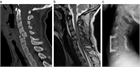

1. CT、MRI:MRIは脊椎と脊髄の同時評価が可能であり有用性が高い。しかし撮像時間を有するならCTを優先させる(推奨度1)